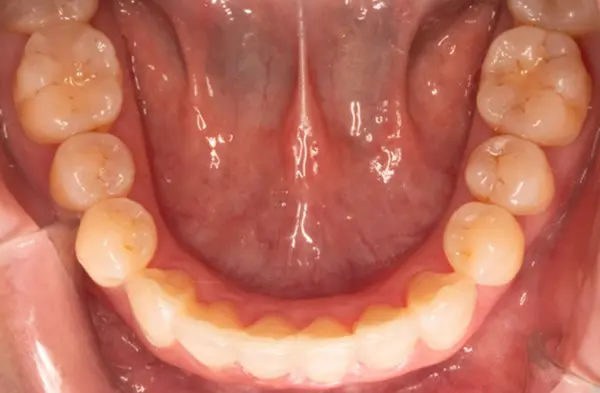

Before

After